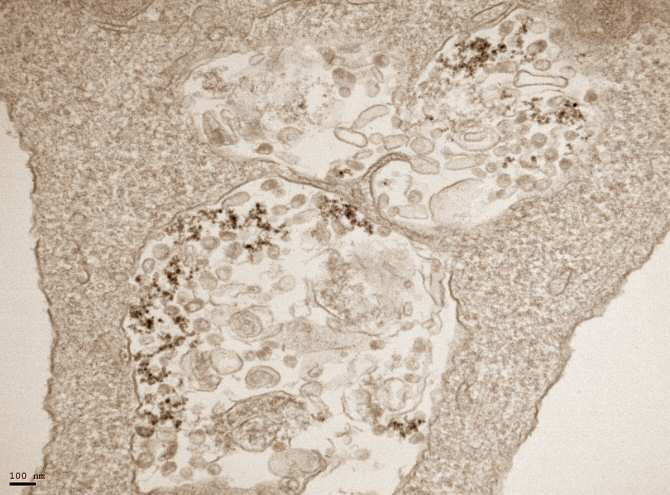

Imagen de microscopía de transmisión electrónica de células infectadas con SARS-CoV-2 y tratadas con nanopartículas de óxido de hierro. (Foto: Yadileiny Portillla y Servicio de Microscopía Electrónica, CNB-CSIC)

Marta López de Diego, también investigadora del CNB, recalca el valor de sus resultados. “El tratamiento de cultivos celulares con nanopartículas de óxido y oxihidróxido de hierro disminuye la replicación viral, tanto cuando las células se tratan con las nanopartículas antes de la infección para prevenirla, como cuando se tratan las células infectadas para eliminar el virus, sugiriendo que estas nanopartículas podrían ser usadas como tratamientos profilácticos y terapéuticos”, explica la investigadora.